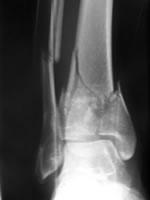

Ankle Fractures